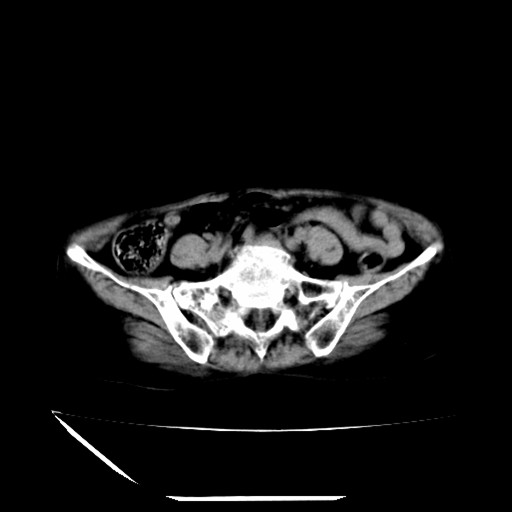

标题: CT16840:女-63岁,下腹部疼痛, [打印本页]

标题: CT16840:女-63岁,下腹部疼痛,

补充资料:血象是13.5,临床拟诊阑尾炎

我觉得你的诊断欠妥;1)右肾周围炎症?是个什么诊断?2)明显的阑尾炎也没看到,最好不要这样写,就是道格拉斯窝内少量积液。

诊断右肾周围炎是因为我图像没有发完,诊断阑尾炎是因为相当于阑尾区连续两个层面可以看到增粗的阑尾显影。

支持阑尾炎!局部腹膜增厚,脂肪密度增高。应该手术治疗。

道格拉斯窝内少量积液。